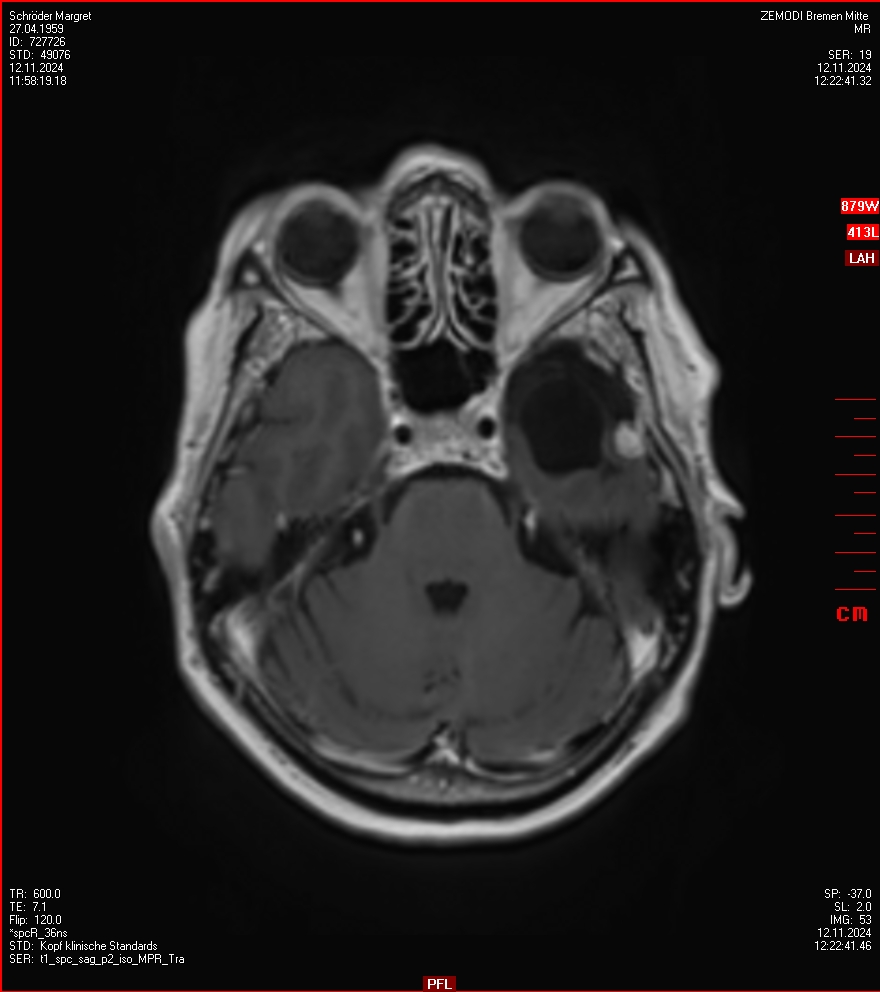

MRT vom 12. November 2024

So nun ein paar neue Bilder aus meinem Kopf. (Durch klicken bekommt man eine größe Ansicht eines Einzelbildes).

Die letzten drei Bilder Zeigen aus meiner Sicht den Tumor, der im Jahr 2021 bestrahlt wurde.